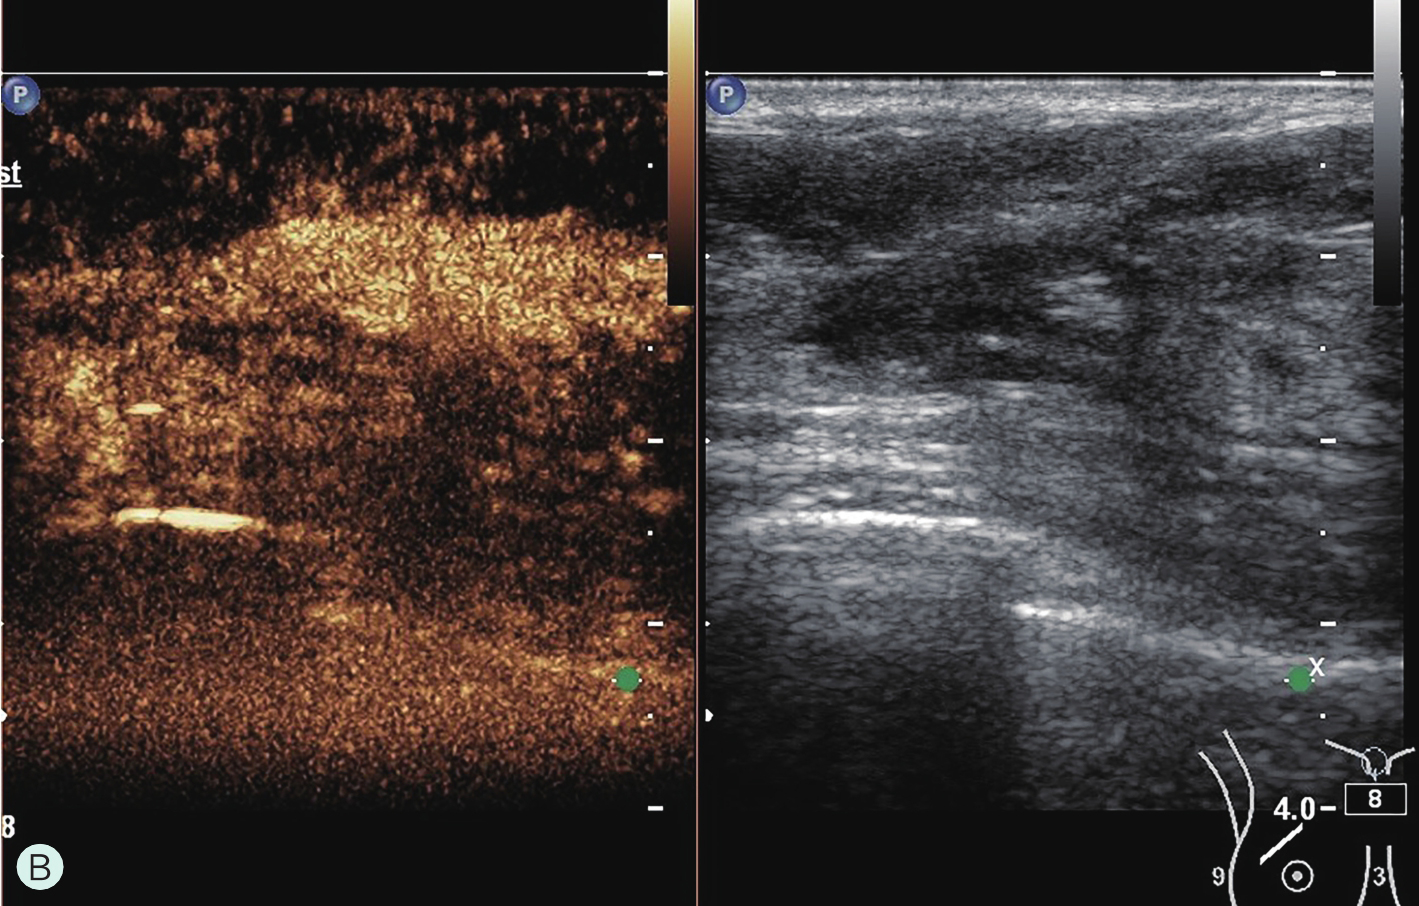

所有具有超声造影功能并支持浅表线阵探头造影的超声诊断仪器均可用于乳腺超声造影检查。由于乳腺超声造影对设备的造影效果、探头选择及参数调节要求很高,故在开展乳腺超声造影前,必须充分论证其造影效果,与设备应用专员共同调节造影参数至乳腺超声造影最佳模式。常规高频线阵探头不能用于乳腺超声造影,而必须选用低频线阵探头。下面将根据笔者所在单位临床工作实际,列举几种超声仪器的乳腺超声造影参数及所用探头供读者参考(图2-1-3~图2-1-7)。

图2-1-7 MINDRAY Resona 8乳腺超声造影参数及所用探头

A.MINDRAY Resona 8乳腺超声造影参数;B.MINDRAY Resona 8乳腺超声造影探头L9-3U